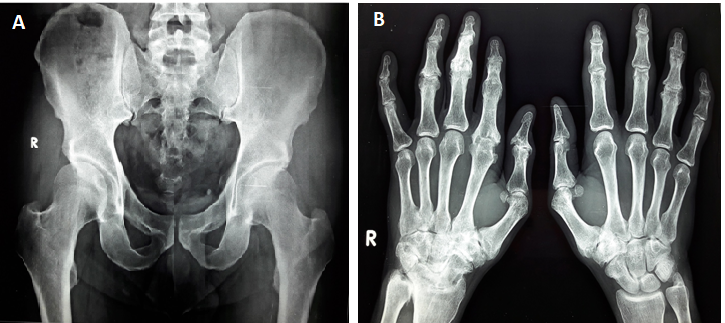

A 52-year-old gentleman with a 25 y history of PsA being treated with oral methotrexate 15 mg/week since 15 y reported with increased joint pains and swelling for the last 9 mo. In addition to PsA, the patient had light-headedness and disturbed bowel movements suggestive of autonomic dysfunction. He is a teetotaler and a non-smoker. He is normotensive and non-diabetic and does not have thyroid dysfunction. He had an elevated erythrocyte sedimentation rate (ESR) of 73 mm/1st hr and high C-reactive protein (CRP) of 25 mg/dl and DAS-28 (Disease Activity Score in 28 joints) score was 6.3 (table 1). Radiographs are depicted in fig. 1. Symptoms of ANS were measured by asking a number of questions according to an easily administered instrument, known as a survey of autonomic symptoms [5].

Fig. 1A: Radiograph of sacroiliac joints, subchondral sclerotic changes are seen in bilateral sacroiliac joints with preserved joint space (Grade II Sacroilitis), fig. 1B. radiographs of hand joints. Reduced bone density changes are seen in bilateral hands. Extensive Erosive Arthritis with loss of Joint space with Subchondral Bone Destruction and Sclerotic changes are seen in right 3rd PIP and DIP joints. Ankylosis changes are seen at right 2nd metacarpophalangeal, PIP and DIP joints. Similar ankylosis changes also seen at left 4th PIP Joint. Joint Space narrowing with subchondral sclerosis is seen at right 1st interphalangeal joint, 4th PIP joint with osteophytes formation. Similar changes also were seen at left 2nd, 3rd and 4th PIP and DIP joints. Erosive arthritic changes also were seen at B/l trapeziometacarpal and 2nd carpometacarpal joints with subchondral sclerotic changes joint space narrowing with sclerotic changes is seen at right Intercarpal joints, radioscaphoid joint and distal radioulnar joint